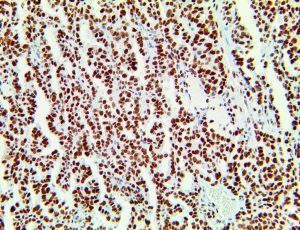

It is the ICU physician who is most likely to witness one of the deadliest manifestations of the abnormal immunological response, the cytokine storm syndrome (CSS). This response is also referred to by some as the cytokine release syndrome (CRS). CSS is characterized by continuous activation and expansion of macrophage and lymphocyte populations, which secrete large amounts of cytokines, causing the cytokine storm. This massive cytokine release is akin to hemophagocytic lymphohistiocytosis (HLH) disease, a syndrome characterized by initial unchecked and persistent activation of cytotoxic T lymphocytes and NK cells.

Clinical and laboratory manifestations of HLH include fever, enlarged liver and/or spleen, neurologic dysfunction, coagulopathy, liver dysfunction, cytopenias (i.e., low levels of erythrocytes, leukocytes, and/or platelets), hypertriglyceridemia, hyperferritinemia, hemophagocytosis, and eventually diminished NK cell activity as the immune system becomes progressively paralyzed. HLH can be familial (primary HLH) or secondary to another disease process (sHLH), such as rheumatic disease, in which it is referred to as macrophage activation syndrome (MAS, characterized by elevated ferritin).